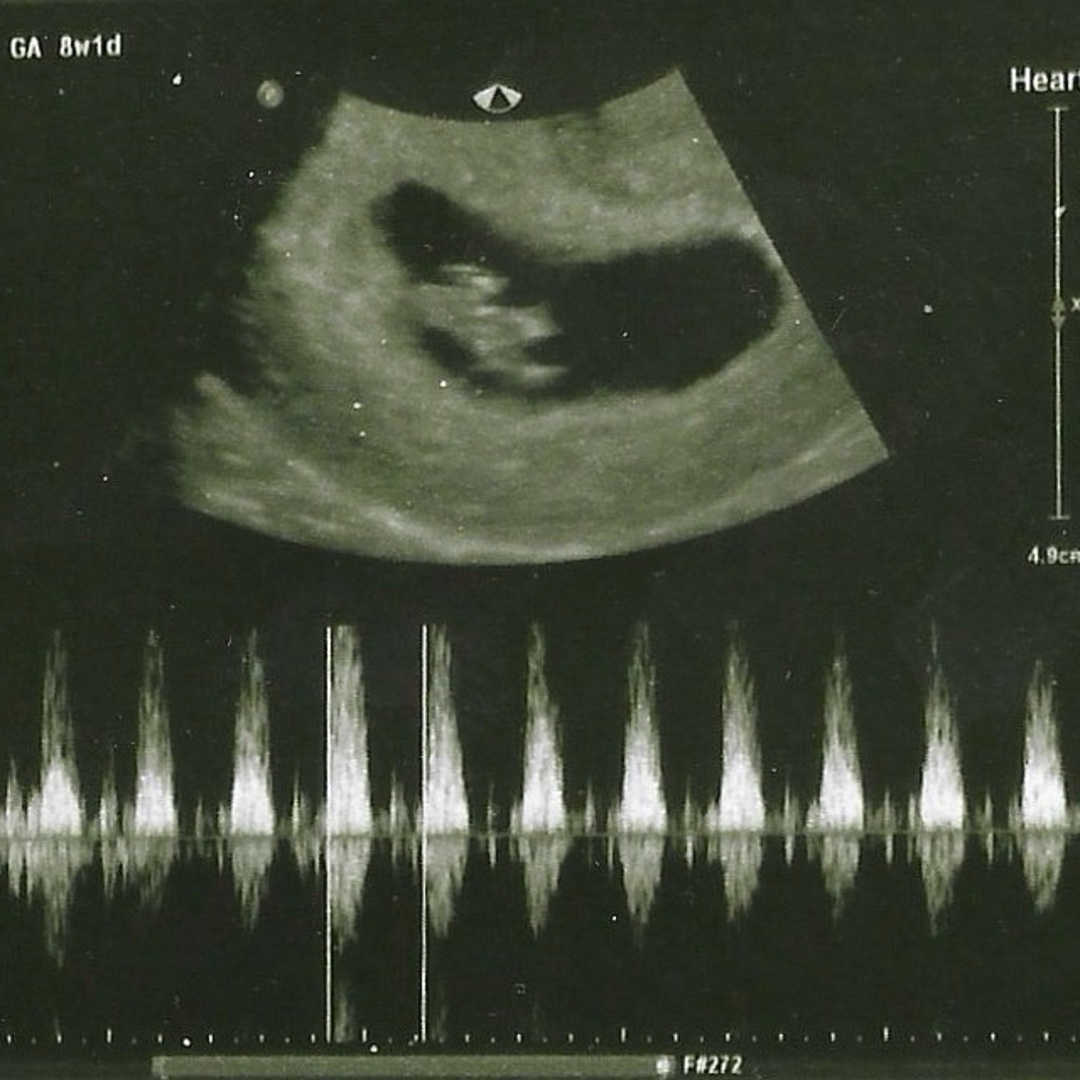

Thank you family! chosen, genetic, near and far. Thank you for your love, support, and for sharing in the joy as we await the arrival of our baby Love. It takes a village and we thank God you are a part of ours. Our girl is so blessed by you and we can't wait for her to meet you!